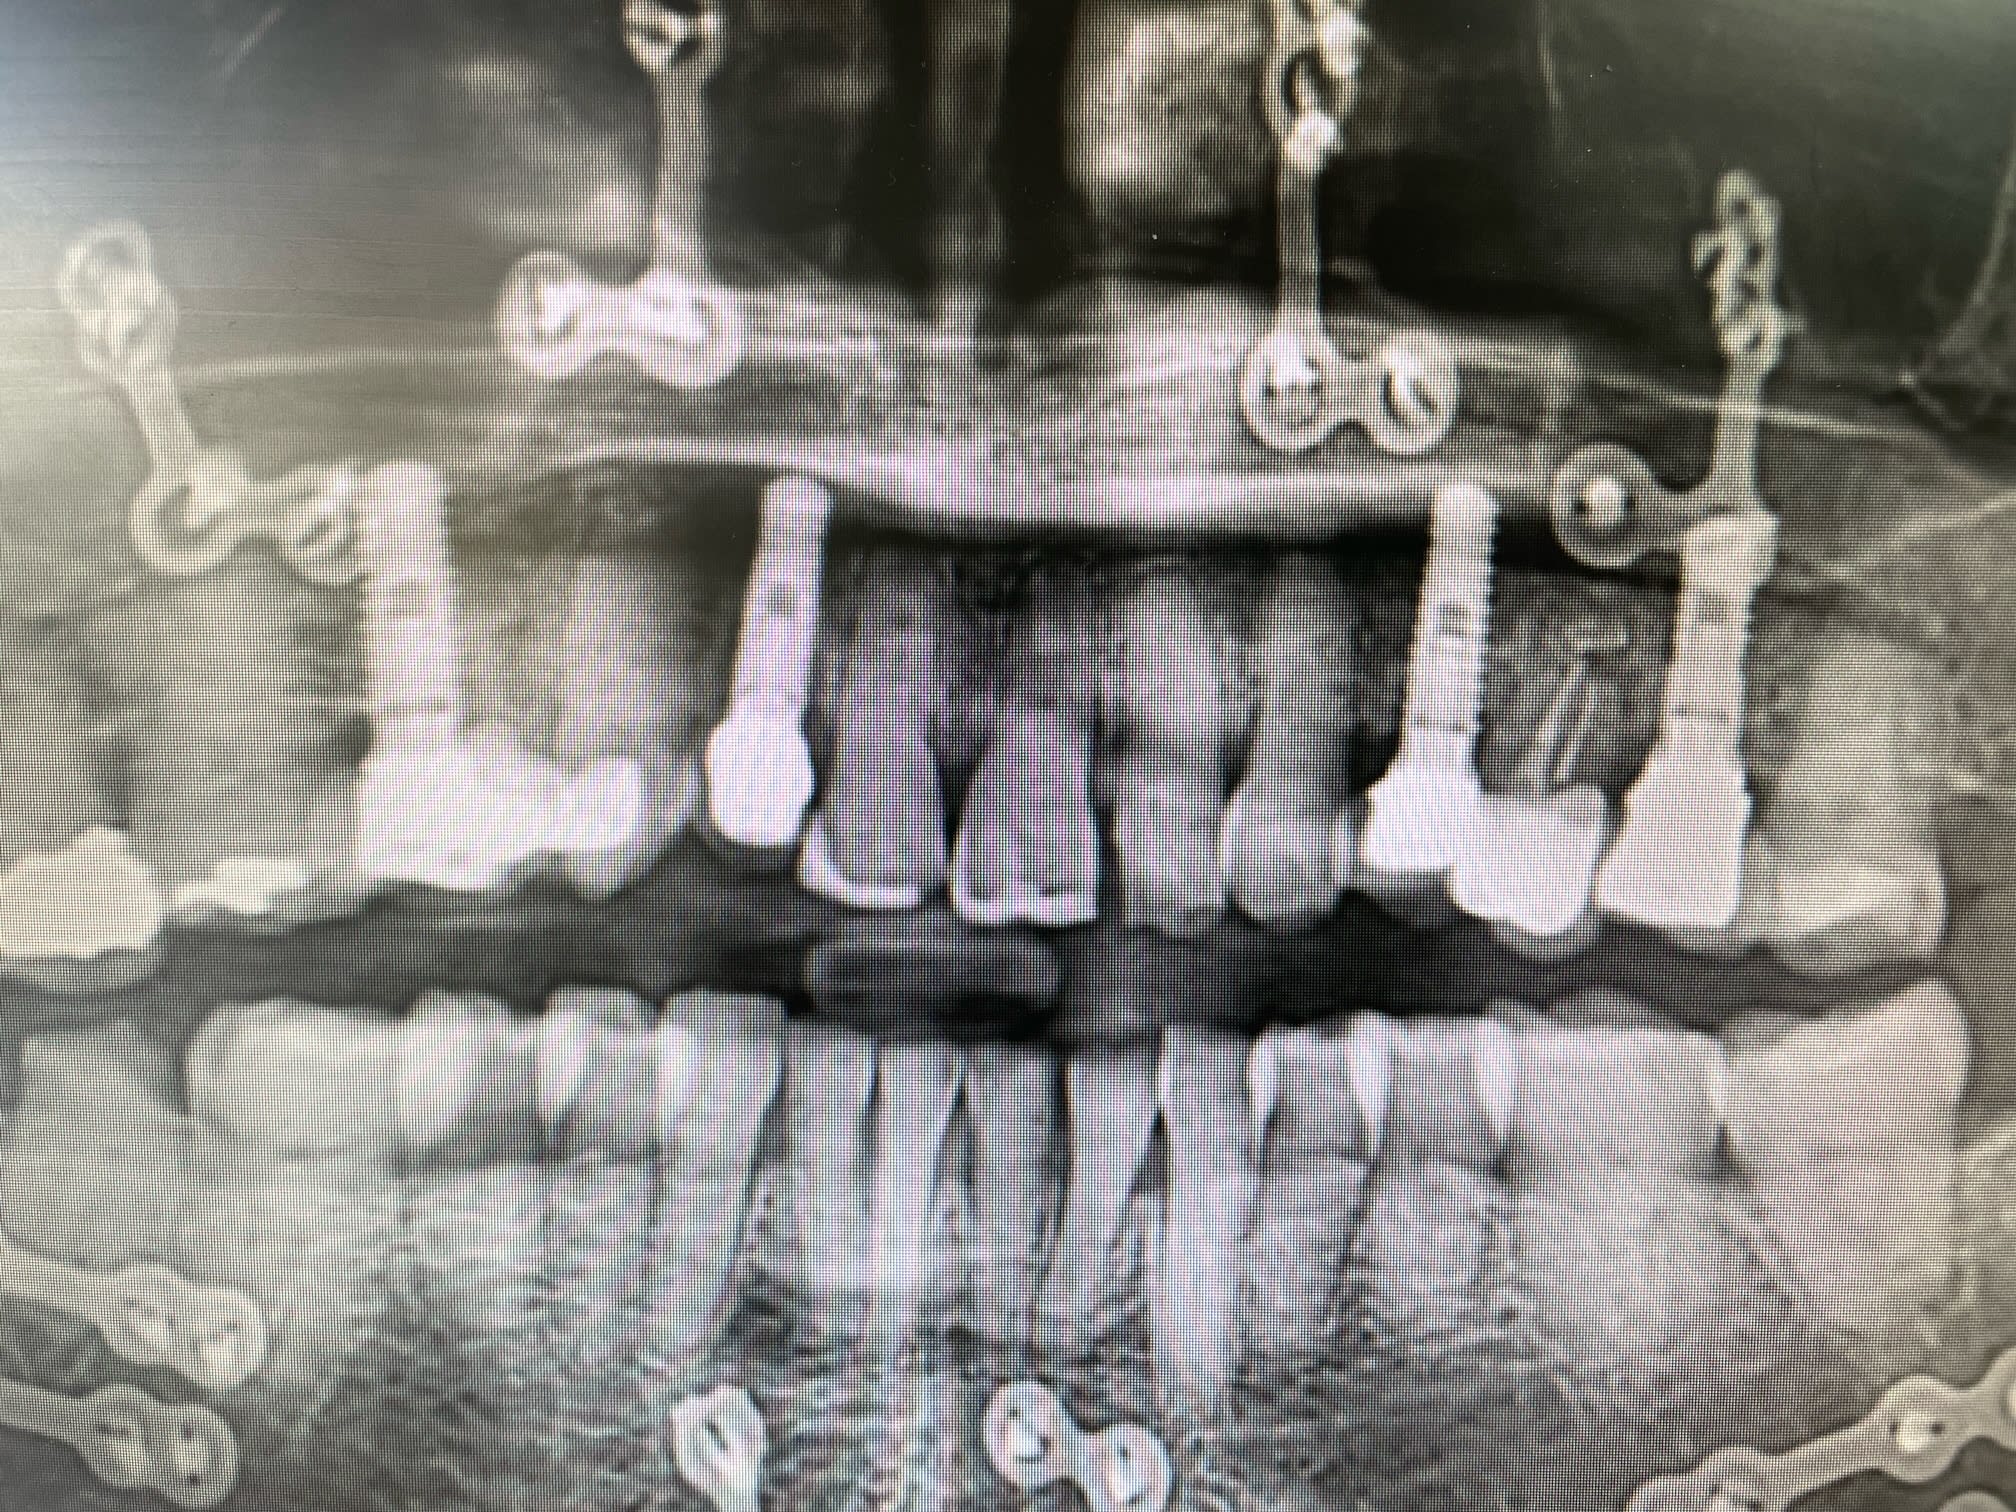

Bonjour, je cherche à confirmer que ces implants sont bien des IDI.

Si oui savez vous avec quelle marque ils sont compatibles et s’il existe des scanbody pour faire de l’empreinte optique?

Pas idi sur . Le seul ressemblant chez idi serait idmax mais il sont different sur plusieurs points

c'est clair.....l'idmax c'est celui qui se rapproche le plus sans cocher toutes les cases....c'est ce qui fait que j'ai pas l'impression que çà soit çà, car les spires semblent différentes.....et pour l'instant, je sèche....

Taille du col et régularité des spires

Des nouvelles de ma galère: les implants sont bien des IDI.

J’ai remis la main sur l’associé du poseur initial. Par contre ce sont des implants qui ont 15 ans. Peut être que la forme a évolué depuis. J’attends la traçabilité exacte la semaine prochaine.

Traçabilité définitive reçue ce matin: IDMAX 4,4. Y a plus qu’à !